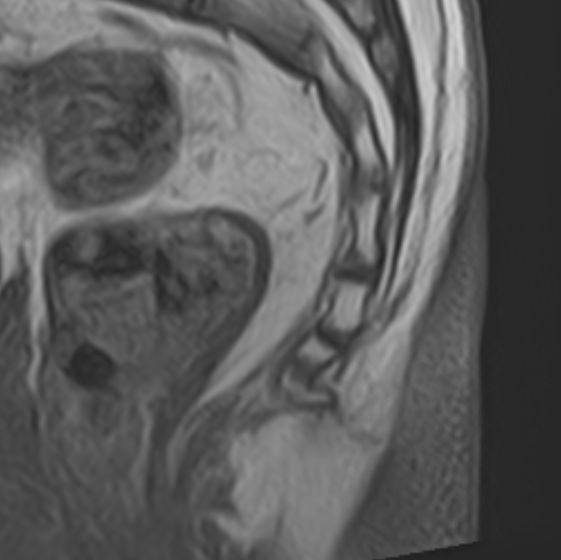

Магнитно-резонансная томография копчика является высокоинформативным методом выявления причин возникновения кокцигодинии. В клинике «Доступная медицина» диагностика осуществляется на новейшем высокопольном томографе закрытого типа TOSHIBA VANTAGE TITAN 1,5 Тесла, обеспечивающем высочайшее качество изображений исследуемой зоны.

Томограф позволяет детально визуализировать как костные структуры копчика, так и окружающие мягкие ткани данной анатомической области, включая мышцы, связки, нервные сплетение, сосуды и прилежащие органы малого таза. МРТ копчика дает возможность диагностировать патологические процессы в самом копчике и выявить их взаимосвязь с патологией окружающих структур.